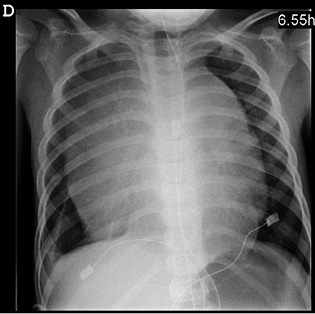

• Obstrucción aérea por adenopatías o ensanchamiento mediastínico (más frecuente en las LAL) (Fig. 1).

Figura 1. Radiografía de tórax antero posterior de un niño de 5 años al debut de una LAL T. Destaca la ocupación del mediastino anterior por una gran masa bilateral.